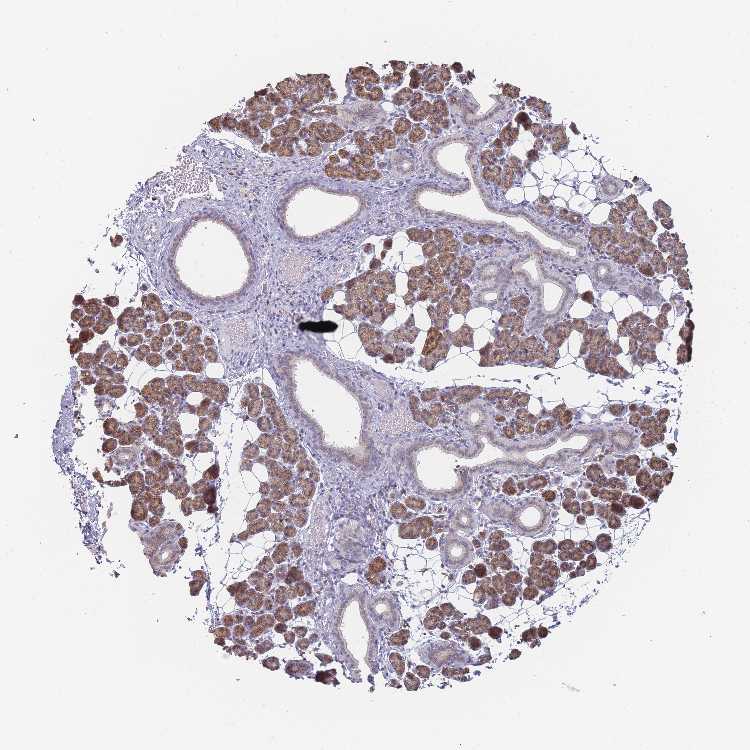

SALIVARY GLAND - Antibody stainingi

Antibody staining in the annotated cell types in the current human tissue is reported as not detected, low, medium, or high, based on conventional immunohistochemistry profiling in selected tissues. This score is based on the combination of the staining intensity and fraction of stained cells.

Each image is clickable and will lead to virtual microscopy that enables deeper exploration of all samples and also displays staining intensity scores, fraction scores and subcellular localization as well as patient and tissue information for each sample.

Antibody HPA047139Antibody HPA050539Antibody CAB034442Antibody CAB037251

Glandular cells HighHighHighHigh